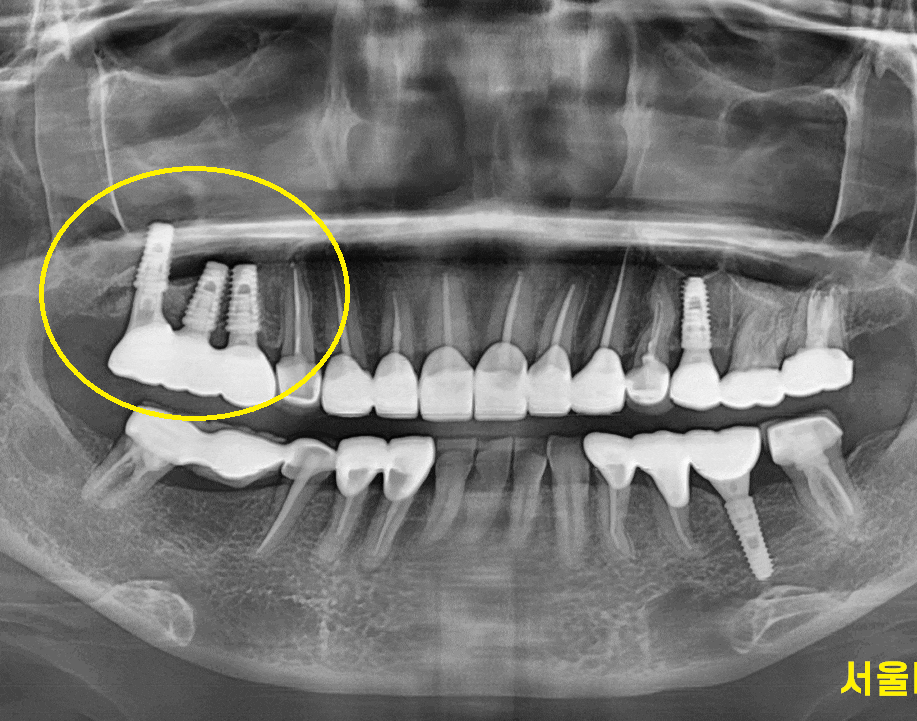

240208

사실상 치아가 제 기능을 다하고 부러진거죠

내부가 까만 것이 다 썩었습니다.

남아있는 치아 부분도 거의 없네요.

사실 이 환자분은 계속해서 저희 병원에서 치료중이셨습니다.

다른 부분을요..

230814

맨 처음 저희 병원 오셨을 때부터

뿌리쪽 충치도 보이고

치아가 안좋지만 뽑기에는 아까우니

쓸 때까지 쓰라고 말씀드렸던 부분입니다.